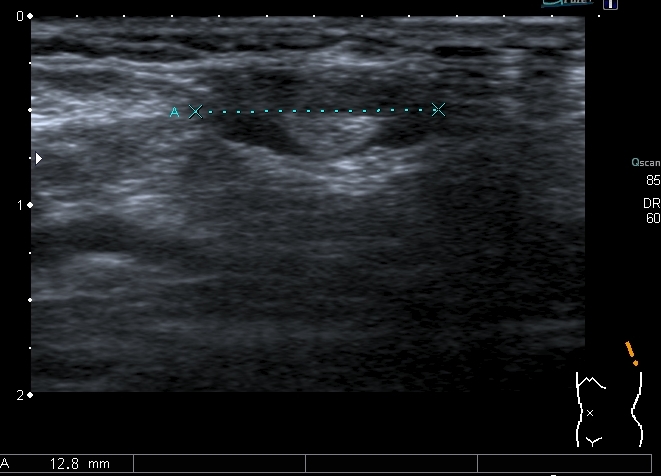

12-years old boy with torax palpable mass 5x3 cm.

Сегодня смотрел мальчика 12 лет, у которого на грудной клетке пальпируется опухоль около 5 см х3 см.

На УЗИ - такая картинка:

Деструкция корткального слоя 7-го ребра с ткаенвым компонетом, исходящим из кости. 7th rib destruction with solid mass

Поперечный скан. Transverse scan